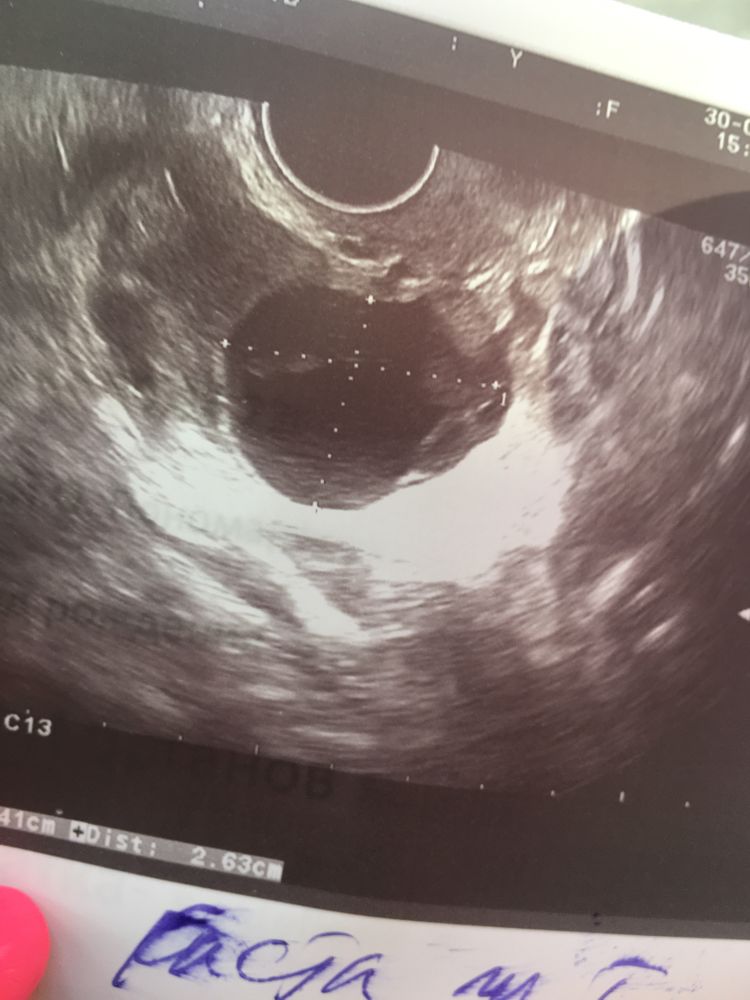

Девочки,все привет) подскажите у кого то была проблема ,как у меня,планируем 5 лет ребёнка ,26.07 была лапороскопия на яичники и сразу через 1,5 недели стали пробовать зачатие,по итогу,к концу цикла заболел яичник ,пошла на узи и вот опять киста ЖТ ,получается беременность не наступила я так понимаю,уже руки опускаю ,что же делать,если даже операция не помогла и овуляция опять не полноценная видимо ,сейчас 6 день задержки ,тянет живот и все пучит ,как будто вот вот пойдут ,узист сказал задержка из за кисты

Мне доктор назначал вобэнзим трижды в день по 2 таблетки, чтоб сама быстрее рассосалась. Конечно, от размера кисты зависит… до 3 см вообще ерунда

Гала, да ,он мне сказал что была ,но типо соответсвует второй фазе цикла ,эндометрий 9 мм ,ждите месячных,врачи блин ,ничего толком нормально сказать не могут,для них не понять,что такое ,когда ты ждёшь столько лет и любой симптом для тебя Надежда